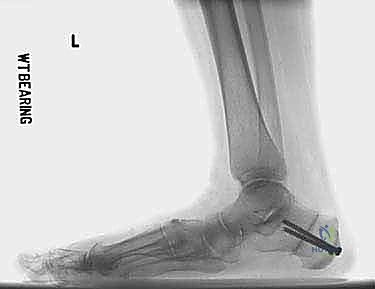

التصوير الطبي والتشخيص الإشعاعي المتقدم

لا يكتمل التشخيص الدقيق دون الاستعانة بأحدث تقنيات التصوير الطبي. يحرص الأستاذ الدكتور محمد هطيف على استخدام نهج شامل يتضمن:

- الأشعة السينية أثناء تحمل الوزن (Weight-bearing X-rays): وهي المعيار الذهبي. يتم أخذ صور من الأمام والخلف والجانبين أثناء وقوف المريض. تسمح هذه الصور بقياس الزوايا بدقة، مثل زاوية ميل الكاحل، وزاوية ميري (Meary's angle)، وتحديد موقع ذروة التشوه.